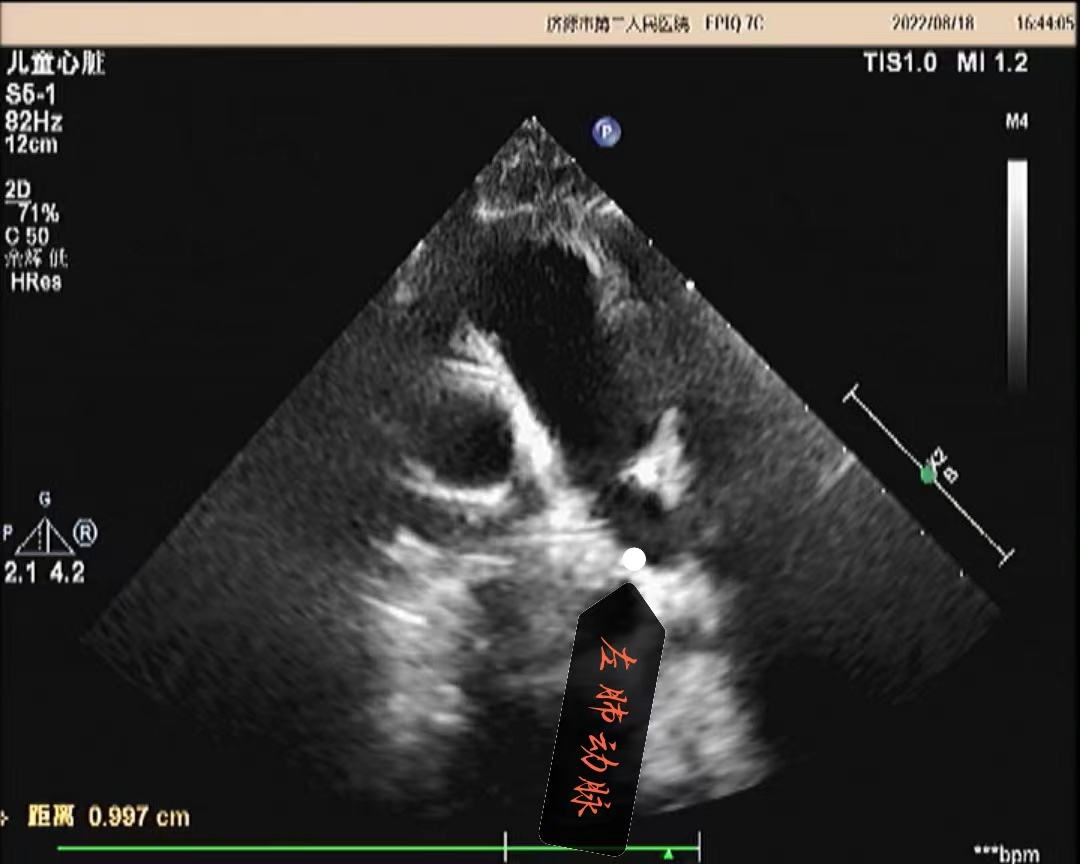

超声所见:各房室大小正常,肺动脉主干内径增宽,约20mm,左右肺动脉内径分别约10mm、8.7mm,左肺动脉起始于主肺动脉的右侧并向左侧走行,右肺动脉起始于主肺动脉左侧向右走行。主动脉内径正常,搏动好。各瓣膜回声正常,肺动脉瓣开启可,关闭欠佳,余瓣膜启闭自如。房室间隔连续完整,室壁厚度及运动收缩幅度正常。CDFI:主肺动脉及左、右肺动脉前向流速增快,主肺动脉峰值流速:2.5m/s、左肺动脉峰值流速:2.2m/s、右肺动脉峰值流速:1.7m/s;肺动脉瓣口探及舒张期少量返流。

超声提示:1.左右肺动脉交叉 2.肺动脉主干内径增宽 3.肺动脉主干及左、右肺动脉前向流速增快 4.肺动脉瓣少量返流

(肺动脉主干及左肺动脉)